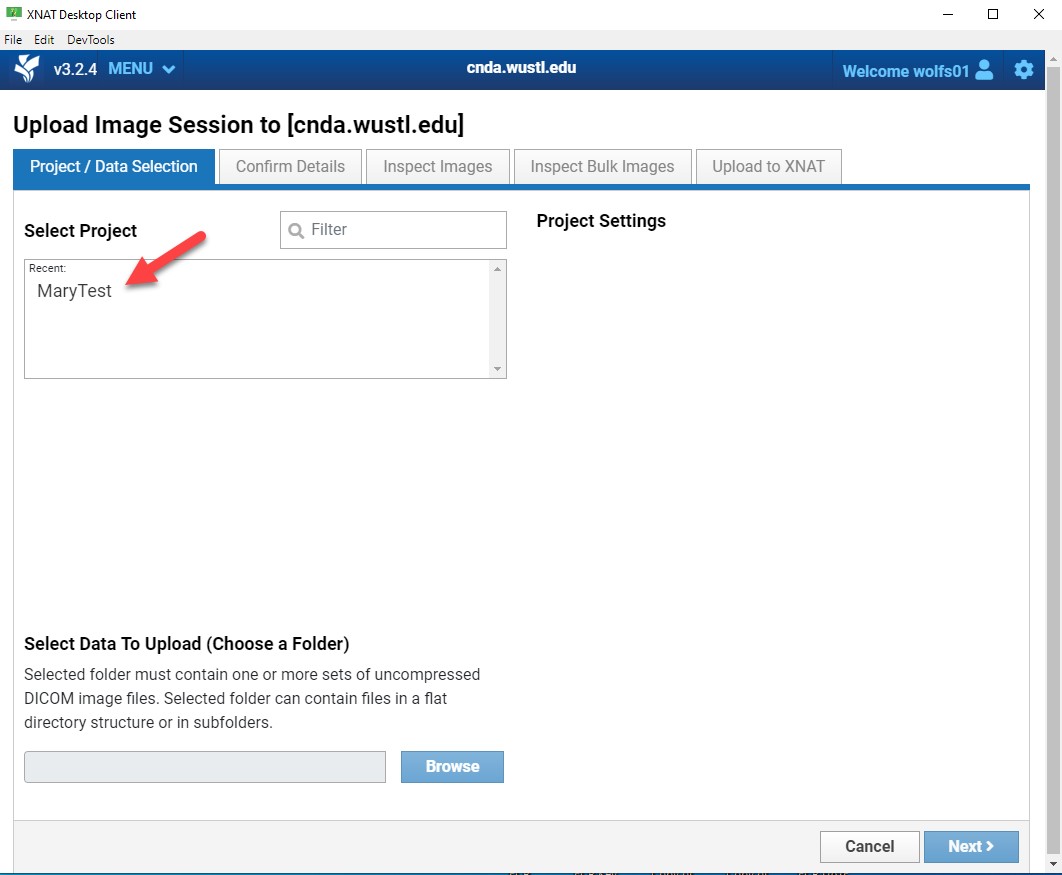

Start Upload

- Click Upload Files.

- Select the destination Project.

Only projects you have access to will appear.

- Click Browse and select the directory containing your image files.